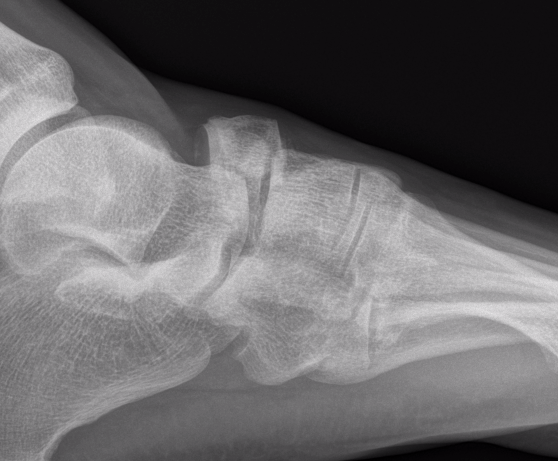

Xray

Displaced navicular stress fracture

Acute, minimally displaced navicular fracture

Acute displaced navicular fracture